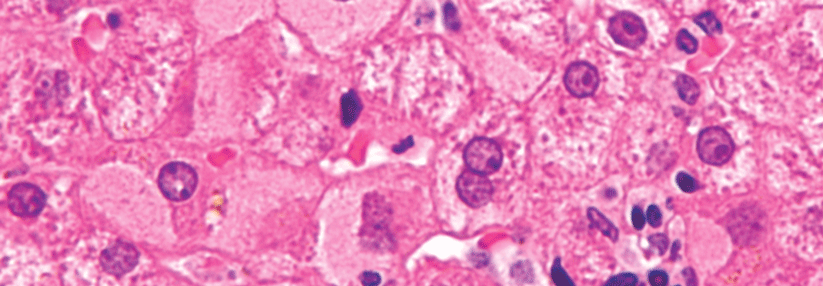

• Leberbiopsie als wichtige Ergänzung, wenn sich Ausmaß und Prognose einer chronischen Hepatitis nicht anders klären lassen